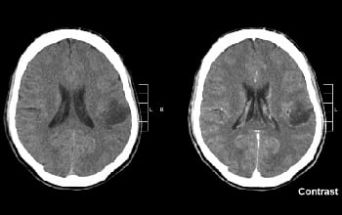

Roma - Il trattamento dei tumori cerebrali rappresenta una delle sfide più difficili in ambito oncologico. I gliomi sono tumori che originano dal sistema nervoso centrale e hanno in Italia una incidenza di 5-6 casi per 100.000 persone adulte per anno (dati AIOM 2018). Si tratta di neoplasie eterogenee e aggressive, per le quali esistono pochi spazi terapeutici, per cui ogni piccolo passo della ricerca clinica che ne migliori la prognosi è da considerarsi un risultato incoraggiante.

Un team multidisciplinare di clinici dell’Istituto Nazionale Tumori Regina Elena ha pubblicato di recente, sulla rivista Journal of Neuro-Oncology, i risultati di uno studio di Fase II che mostrano i benefici di un chemioterapico, per lo più utilizzato nella cura dei tumori cerebrali pediatrici, in pazienti adulti con glioma maligno in recidiva dopo trattamenti chemioterapici standard.

Lo studio ha dimostrato che la somministrazione settimanale del chemioterapico, il carboplatino, ha determinato un controllo della malattia in oltre il 30% dei pazienti e una durata della risposta alla terapia di oltre 7 mesi. I pazienti che hanno tratto beneficio dal trattamento hanno mostrato non solo un ritardo alla progressione di malattia ma anche un tempo più lungo di sopravvivenza rispetto ai pazienti che non hanno risposto al farmaco.